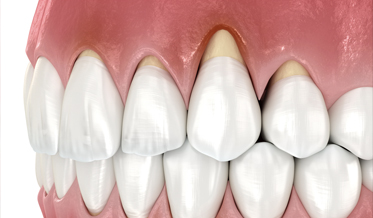

Soft-Tissue Reconstruction at Anterior Implant Sites With Soft-Tissue Dehiscences

Advances in Esthetic, Immediate Tooth Replacement Therapy Aimed at Improving Clinical Outcomes

Barry P. Levin, DMD